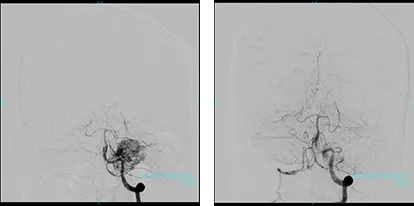

開頭脳腫瘍摘出術前の腫瘍栄養血管塞栓術

腫瘍が血管に富む場合、開頭摘出術中の出血量を軽減する目的で、カテーテルによる腫瘍栄養血管塞栓術を行うことがあります。

左小脳に造影剤によく染まる腫瘍を認めます。

左は塞栓術前、右は塞栓術後、造影剤が入る範囲が縮小しています。

左は塞栓術前、右は塞栓術後

回転DSA:立体的に見える画像では塞栓術前後での違いがより分かりやすくなります。